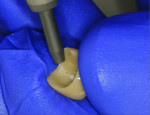

Two weeks later, the patient presented for a try-in of the final restoration, at which time a hemostat was used to remove the temporary crown (Figure 1). To completely remove the residual cement, pumice was used in a prophy cup to thoroughly clean the area (Figure 2). The try-in of the restoration entailed checking for marginal integrity, proper interproximal contacts, and an ideal occlusal relationship (Figure 3). Following this, all necessary adjustments were made utilizing a fine diamond football-shaped bur (285.5Z-TSZtech, Premier Dental).